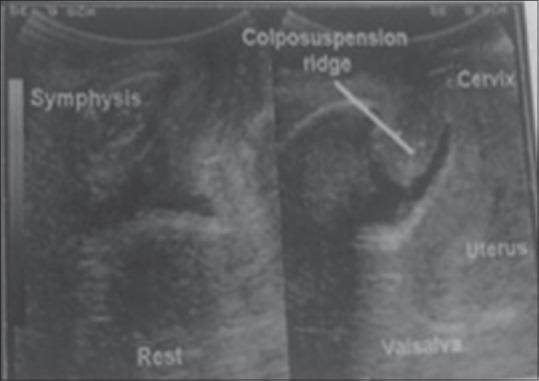

Materials and methods: It is a prospective study conducted over 40 women of SUI by endovaginal ultrasound on rest and Valsalva preoperatively and 6 months postoperatively for levator hiatus (LH), pubovisceral thickness, urethral length, and bladder neck (BN) position. A 24 h pad test was also performed on all women at the same time for grading of SUI. Treatment given was medical in 4 (10%), Burch colposuspension in 18 (45%), and tension-free obturator tape in 18 (45%).

Results: The mean age, parity, and body mass index in the study were 41.60 years, 2.73, and 24.2 kg/m2, respectively. All 40 (100%) patients had SUI with a mean duration of symptoms being 4.04 years. On 24 h pad test, mild SUI was in 4 (10%), moderate SUI in 33 (82.5%), and severe SUI in 3 (7.5%) with mean preoperative 24 h pad test being 36.69 g which significantly reduced to 9.79 g postoperatively (P = 0.001). There was significant change in LH and pubovisceral thickness with treatment of SUI. Overall urethral length increased but there was significant decrease in urethral length on Valsalva after the treatment (0.40 cm vs. 0.28 cm, P = 0.04) and significant reduction in BN descent after Valsalva after treatment (0.41 cm vs. 0.27 cm, P = 0.001).